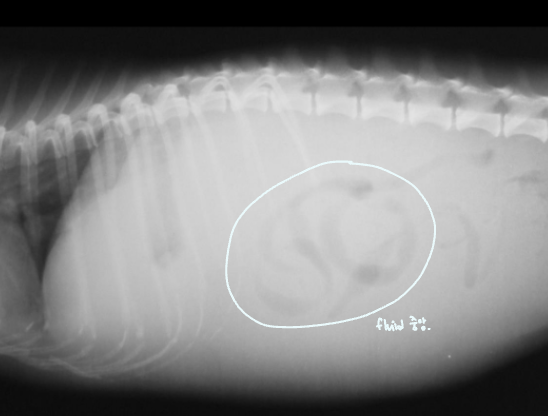

Fluid or Mass

- Fluid : ์ธ์ธก์์์ ์ค์์ผ๋ก ๋ชจ์. diffuseํ ์ฐ๋ถ์กฐ์ง ๋ฐ๋.

- Mass : ์๋ฆฌ๋ฅผ ์ฐจ์งํจ โ ์ฅ์ ๋ฐ์ด๋. & ์ข ์์ด ์ปค์ง๋ฉด์ ์ถํ์ ์ ๋ฐ.